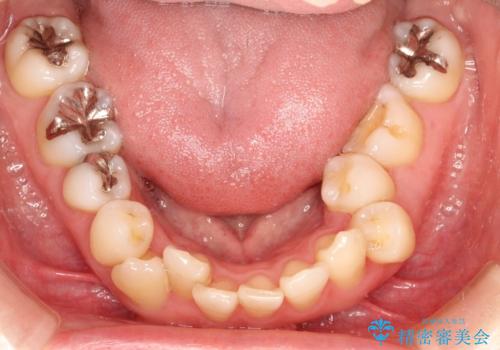

上下のガタガタのマウスピースによる非抜歯矯正

- 上下のがたつきを主訴に来院された患者様です。

上下の前歯と奥歯にがたつきがありました。

上下の奥歯を後方に移動させるのと、歯と歯の間をわずかに削ることでスペースを作り、歯を並べる計画としました。